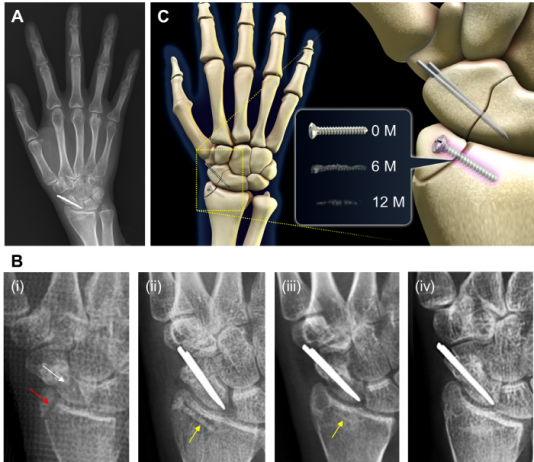

빙판길 낙상사고가 급증하는 계절, 낙상을 포함하여 사고로 인해 골절 환자가 증가하고 있다. 골절 부상은 보통 부러진 뼈를 고정하는 장치를 사용하여 수술하게 되는데, 몸속에 남아있는 금속 임플란트로 인해 우리는 부작용을 겪거나 불편함을 경험하게 된다. 국내 산학연병 공동연구진이 이러한 문제를 해결할 수 있는 생분해성 금속 정형외과 임플란트를 개발하였다. 생분해성 금속은 체내...